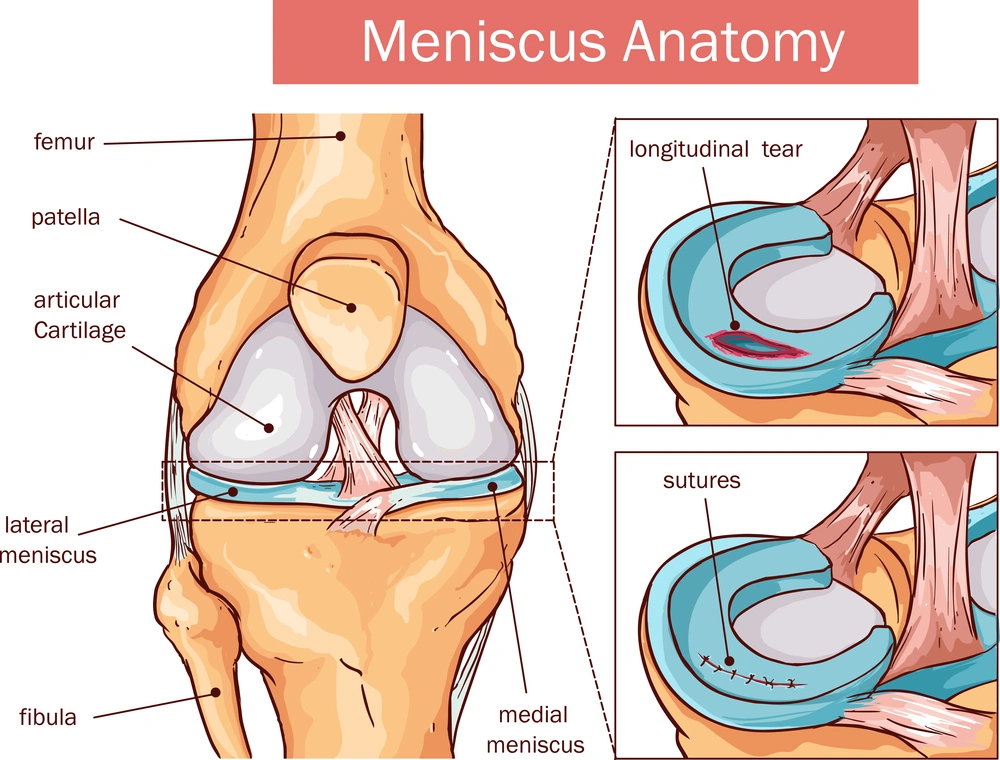

Cartilage repair procedures are often minimally invasive, performed through small arthroscopic incisions using advanced imaging and surgical navigation systems. Microfracture surgery stimulates new cartilage growth by creating small holes in the underlying bone, while ACI involves growing healthy cartilage cells in a lab before implanting them in the damaged area. Osteochondral grafting replaces damaged tissue with healthy cartilage and bone from the patient or donor. Recovery includes early physical therapy to restore strength, flexibility, and range of motion, with gradual progression of weight-bearing under professional supervision. Most patients experience significant improvement in function and reduction in pain within weeks to months, depending on the procedure and extent of damage.

Common techniques include microfracture surgery, autologous chondrocyte implantation (ACI), and osteochondral grafting, each tailored to the location and extent of cartilage damage.